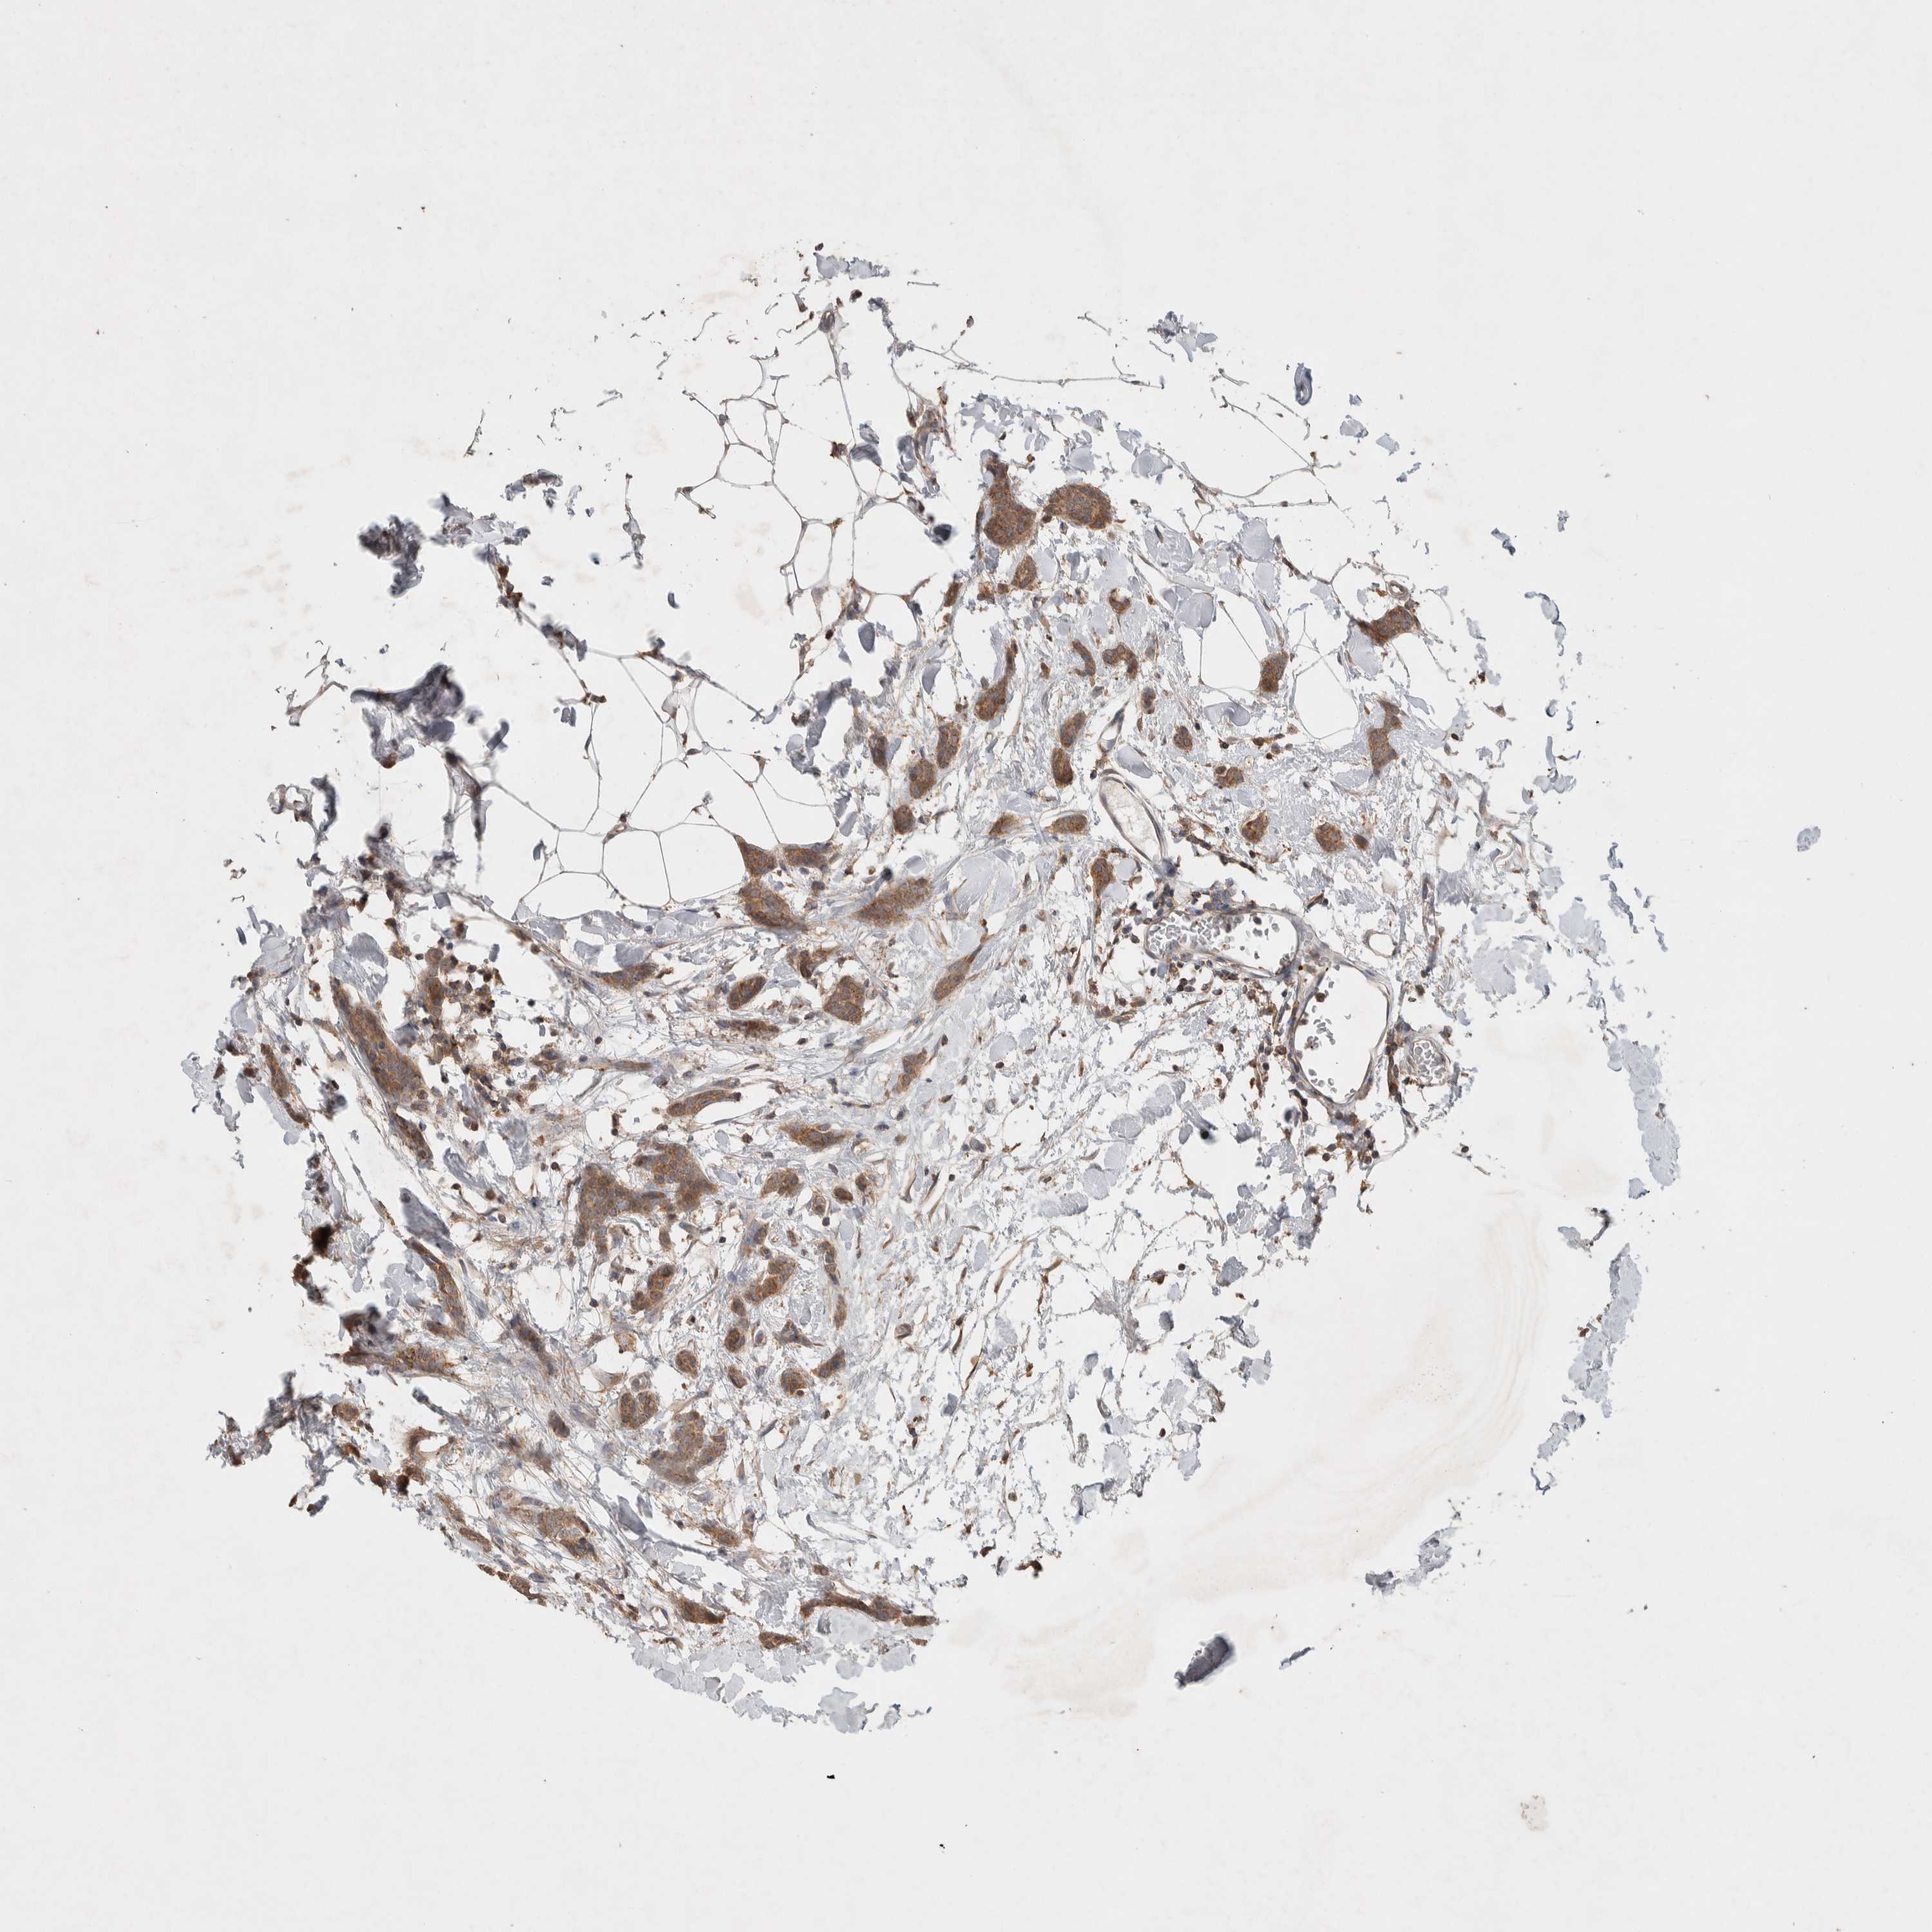

BRCA TCGA BRCA VALIDATION PROTEIN EXPRESSION